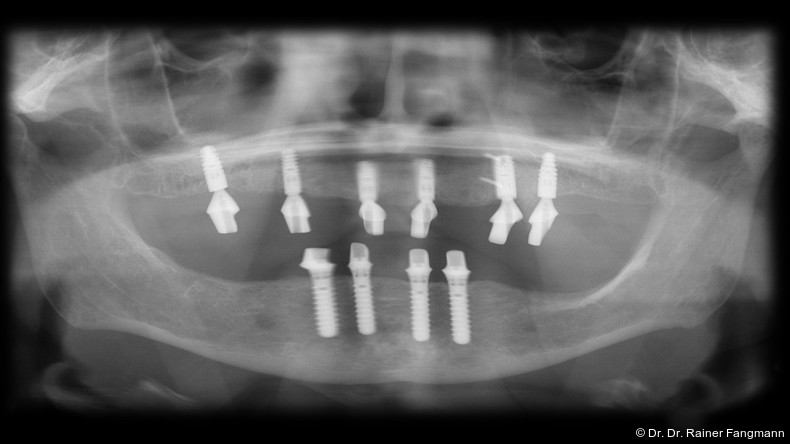

Der atrophierte Unterkiefer bietet in der Regel ein nicht ausreichendes Lager. Die totalprothetische Versorgung des zahnlosen Oberkiefers bedingt stets eine gaumenbedeckende Konstruktion. „Der Platz, der dem implantologischen Chirurgen für die Positionierung der Zahnimplantate zur Verfügung steht, kann durch anatomische Gegebenheiten wie einen stark pneumatisierten Sinus maxillaris oder einen eher koronalen Verlauf des Canalis mandibularis eingeschränkt werden.“ Zudem kann das in vertikaler und horizontaler Ebene reduzierte krestale Knochenvolumen mit und ohne schlechte Knochenqualität den Therapieansatz noch weiter verkomplizieren. So ist seit 2000 das Konzept der schräginserierten Implantate entstanden und verfolgt worden.3 Eine von Zampelis et al. durchgeführte In-vitro-Studie hat bewiesen, dass eine schräge Insertion von prothetischen verblockten Implantaten nicht zu einer größeren Belastung führt als bei parallel gesetzten Implantaten.3 Die Digitalisierung der Zahnmedizin und -technik und der zunehmende Wunsch der Patienten nach festsitzenden Versorgungen führten zudem zu einer vermehrten Verbreitung dieses nach seinem Erstbeschreiber Maló benannten Konzeptes. Ebenso haben immer mehr Implantatanbieter die spezifischen abgewinkelten Aufbauelemente in ihr Portfolio aufgenommen. „In prothetischer Hinsicht ist es letztlich auf einer geringeren Anzahl von Implantaten einfacher, eine spannungsfreie Passung der Stege zu erreichen.“

Es war die Arbeitsgruppe um den Zahnarzt Paulo Maló und den Biomechaniker Bob Rangert, die das Konzept der angulierten Implantate zur Versorgung mit festsitzenden Brücken im Unterkiefer klinisch etablierten.4, 5 Der Ausgangspunkt dieser Methode ist eine großflächige Abstützung auf einem breiten prothetischen Polygon. Erzielt wird das durch die Angulierung der distalen Implantate. Die Arbeiten von Maló und Rangert demonstrierten eine kumulative Überlebensrate von über 96 Prozent bei einer prothetischen Überlebensrate von 100 Prozent und erbrachten damit den Nachweis, dass vier Implantate einer festsitzenden Brücke im Unterkiefer stabilen Halt geben. Behandlungsabläufe mit multiplen chirurgischen Eingriffen sind für Patienten anstrengend, beschwerlich und bedeuten eine Einschränkung der Lebensqualität. Die Methode von Maló und Rangert konnte durch die Nutzung des vorhandenen Knochenangebots und einer Sofortversorgung den gesamten Behandlungsablauf auf lediglich eine Sitzung reduzieren und folglich die Patientenakzeptanz deutlich erhöhen. Heute wird das Konzept der Sofortversorgung mit reduzierter Implantatanzahl oftmals um einen digitalen Workflow erweitert. Die Firma Dentsply Sirona bietet mit dem SmartFix-Konzept des Ankylos® C/X-Systems oder mit der EV-Prothetik der Systeme Astra Tech Implant System®, PrimeTaper® und OmniTaper® spezielle Aufbauten für diese Technik an.